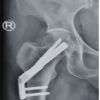

A 60-year-old male patient with TYPE 31-A2.2 pertrochanteric femur fracture of the right side (Fig. 4).

Figure 4: (a) Pre-operative anterior-posterior (A-P) view X-ray showing TYPE 31-A2.2 pertrochanteric femur fracture of the right side. (b) Post-operative A-P view X-ray showing pertrochanteric femur fracture fixed with short proximal femur nail.